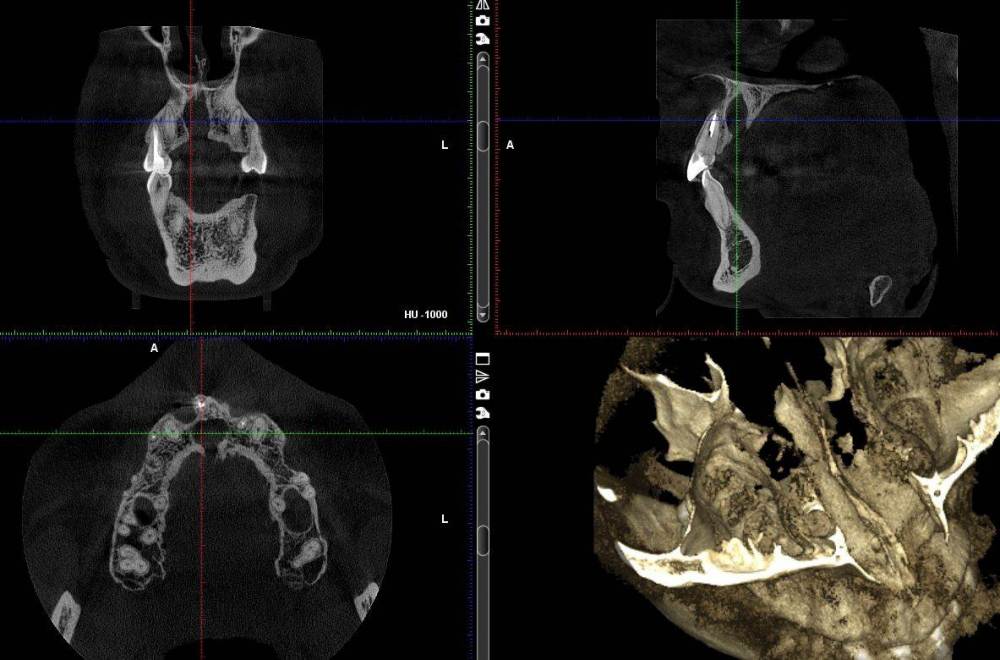

tati_dom Опубликовано 12 мая, 2021 Поделиться Опубликовано 12 мая, 2021 (изменено) Добрый день! Подскажите что это вообще такое, что с этим делать. Прием у врача только завтра. М. 26 лет, в 10 лет был удален лишний по количеству зуб, который рос вторым рядом. Как сказал тогда врач зуб был достаточно большим. Сейчас после небольшой простуды, сильно заболел толи зуб толи десна, с температурой до 38, плохим самочувствием. Сначала перелечили передние зубы, к вечеру стало хуже, вернулись в клинику, назначили антибиотики послали на КТ. После антибиотиков стало легче. На КТ такая картина. Зуб был удален на месте этой "дырки", не срослась кость за эти годы? Изменено 12 мая, 2021 пользователем tati_dom Ссылка на комментарий

сирена Опубликовано 12 мая, 2021 Поделиться Опубликовано 12 мая, 2021 Это называется "Киста резцового канала",она удаляется хирургически. Ссылка на комментарий